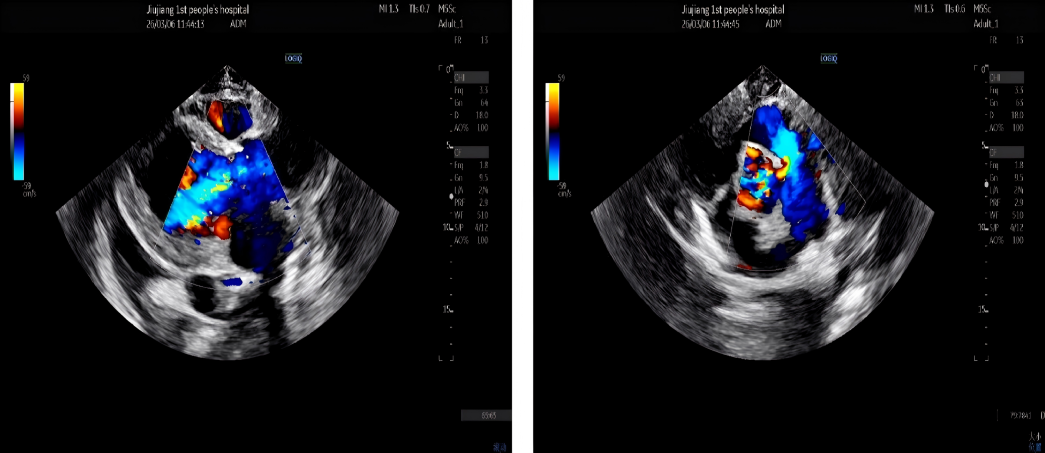

73岁的患者于婆婆(化名)因重度主动脉瓣狭窄入院,突发急性失代偿性心衰合并心源性休克,血压持续走低,多器官功能急剧恶化,此类患者24小时内死亡率超50%,急诊TAVR是唯一的生存希望。术中造影发现,患者双侧股动脉最细处直径不足3毫米,远达不到手术输送鞘管的最低要求,常规入路完全阻断;开胸心尖入路创伤过大,休克状态下的患者根本无法耐受,所有常规方案均不可行。更棘手的是,患者病情危重无法完成术前主动脉CTA检查,手术团队只能在“半盲”状态下,仅凭有限影像和临床经验,完成毫米级的精准操作。

生死关头,在与患者家属充分沟通后,心血管诊疗中心一病区主任敖钦主任医师、主诊组长曹俊达副主任医师迅速集结心内、胸外、超声、麻醉、介入护理等多学科团队,并调动重症ECMO团队全程为手术保驾护航。团队选择经左侧颈总动脉入路,而这一术式,在急诊抢救、无术前CTA精准导航的双重极限条件下,无疑是一场超高难度的生死挑战。颈动脉是大脑供血命脉,操作稍有闪失即可引发灾难性卒中;无CTA就无法评估血管内斑块、走行异常、主动脉弓部情况,每一步都是“雷区”。心胸外科诊疗中心陈世雄副主任医师团队精准暴露左侧颈总动脉,穿刺、置管一气呵成。术中仅凭食道超声即时评估选择瓣膜型号,导丝“盲穿”穿过主动脉弓进入左心室。从穿刺到瓣膜释放,全程仅用时13分钟。造影显示瓣膜位置完美,无瓣周漏,冠脉通畅。术后患者血压即刻改善,次日心功能明显恢复,第五天转回普通病房,康复顺利。